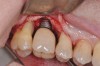

The main objective of peri-implant mucositis treatment is the resolution of inflammation.18 Oral healthcare providers should employ a two-pronged approach in the treatment of peri-implant mucositis. First, they should consider the patient's ability to perform adequate oral hygiene around the implant prosthesisthis includes assessing the patient's accessibility to the area in the mouthand prescribe appropriate aids in biofilm removal (Figure 1 and Figure 2). Second, the clinician should institute mechanical therapy and an appropriate peri-implant maintenance regimen consisting of further evaluation and treatment, if needed.

Fig 1. Patient presented with a screw-retained, full-arch restoration with full flange extension. Note there was no access for oral hygiene.

Figure 1